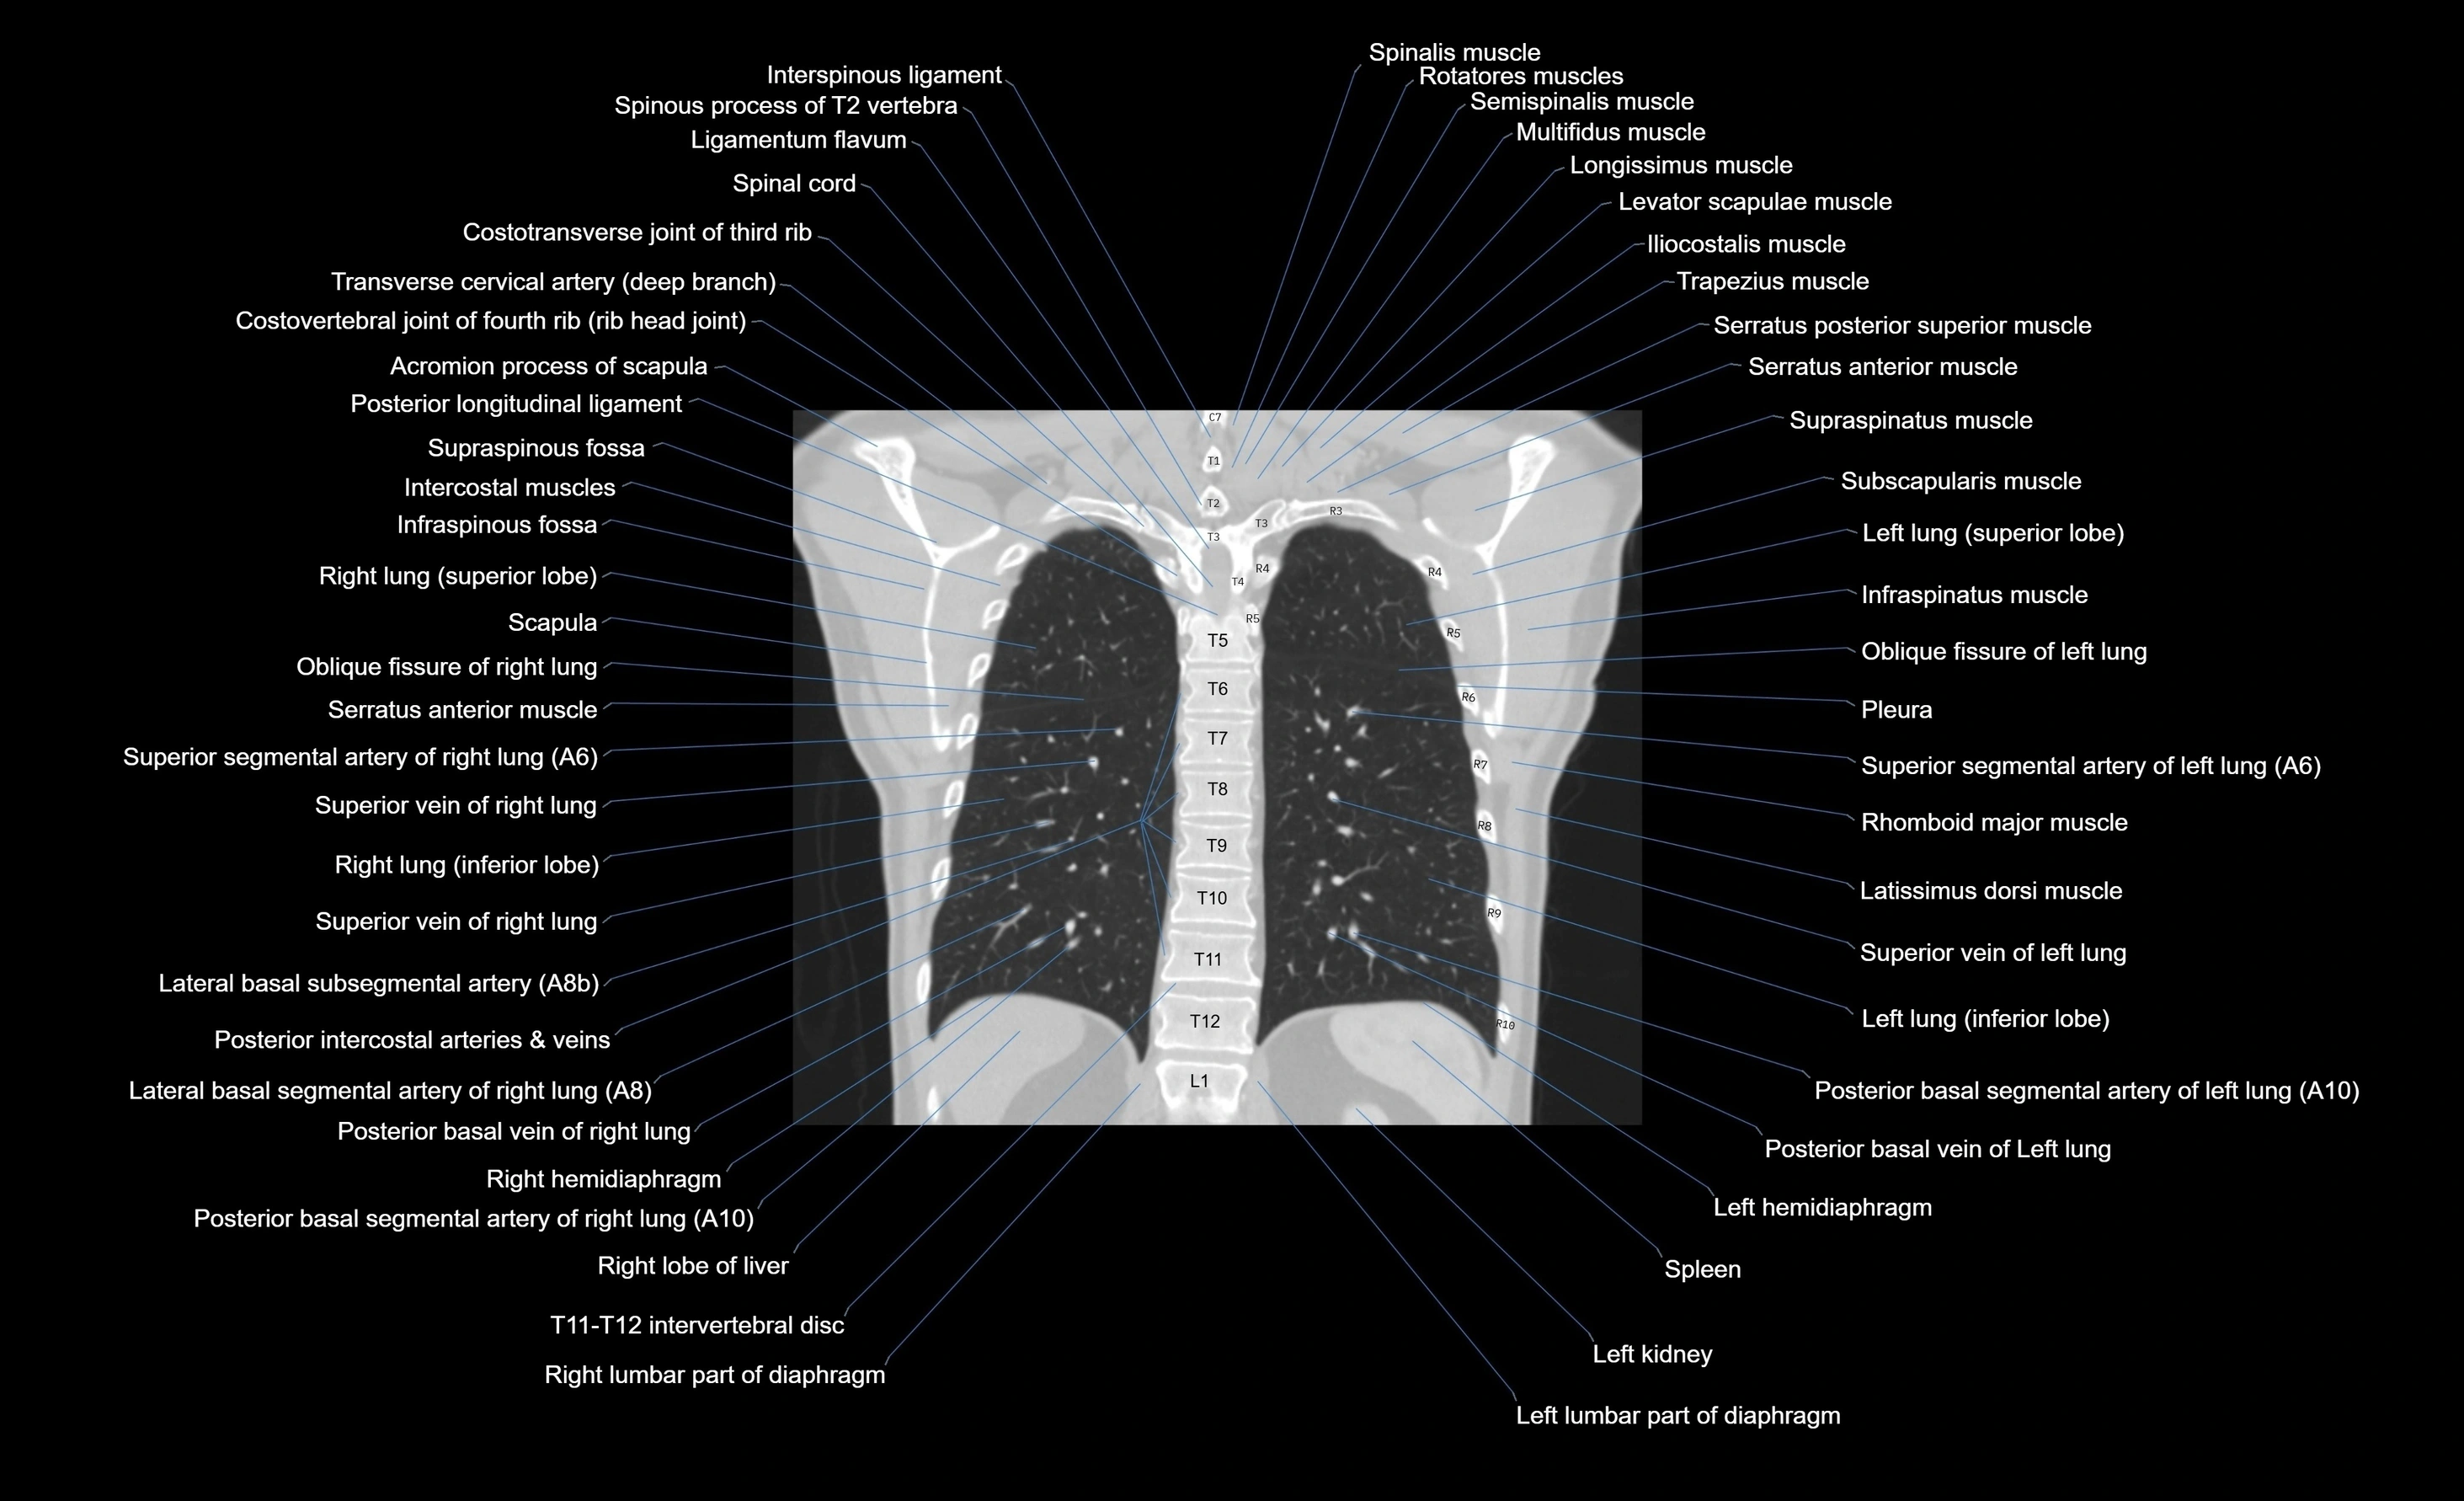

- T (Thoracic spine)